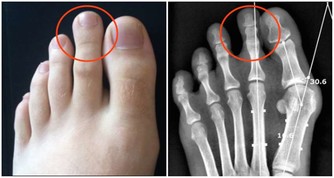

3、糖尿病患者

糖尿病分為神經病變型、缺血型、和混合型。神經病變型的部分患者,可以表現為腿足感覺奇冷,怕冷。因此,熱水泡腳很容易,成為一個舒適的選擇。悲劇在於:神經病變一旦存在,患者對痛覺、水溫的感覺,反饋機制失靈。因此患者往往會不斷加熱水,哪怕已經嚴重燙傷,也渾然不知。

而缺血型糖尿病足患者面臨的問題,則與上面提到的動脈閉塞症患者的情況相似。

所以假如患有以上這些病症,就建議不要天天泡腳,非旦不能養生,還可以致殘!